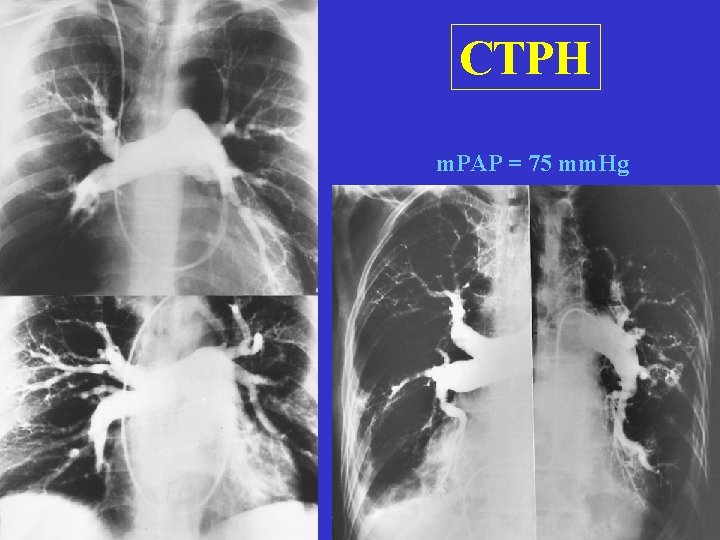

Clinical classification Hemodynamics (mm. Hg): RA 1. Acute, massive 2. Acute, minor 3. Chronic, reccurant (CTEPH) 12 5 6 RV PA 45/0 -12 45/20 30/0 -5 30/15 90/0 -6 90/50

Chronic, reccurant PE (CTEPH) • • Reccurant episodes for months - years Progression of effort dyspnea Cyanosis Angina-like chest pain (decreased myocardial perfusion pressure) • Tachycardia, PII !, systolic ejection click • Death: progression of right heart failure Diff dg: COPD, CHF, hyperventilation sy

CTPH m. PAP = 75 mm. Hg